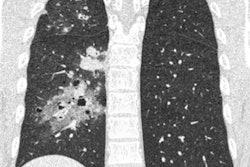

When analyzing the results, the investigators found that the ultrahigh-resolution CT scans had twice the spatial resolution of the conventional CT scans and considerably superior overall image quality, despite increases in image noise.

| Ultrahigh-resolution vs. conventional CT for assessing in-stent restenosis | ||

| Conventional CT | Ultrahigh-resolution CT | |

| Spatial resolution at 10% modulation transfer function | 12.5 lp/cm | 24.3 lp/cm |

| Spatial resolution at 2% modulation transfer function | 14.3 lp/cm | 29.1 lp/cm |

| Overall image quality* | 2 | 3 |

| Mean error rate of vessel diameter measurements* | 16.9% | 8% |

| Diagnostic accuracy from 2 readings | 72%; 94% | 81%; 97% |

What's more, ultrahigh-resolution CT allowed the radiologists to measure the narrowed segments within the blood vessel phantoms with fewer errors compared with conventional CT (p < 0.001). The newer scanner was also associated with a moderately higher accuracy for the detection of stenosis.